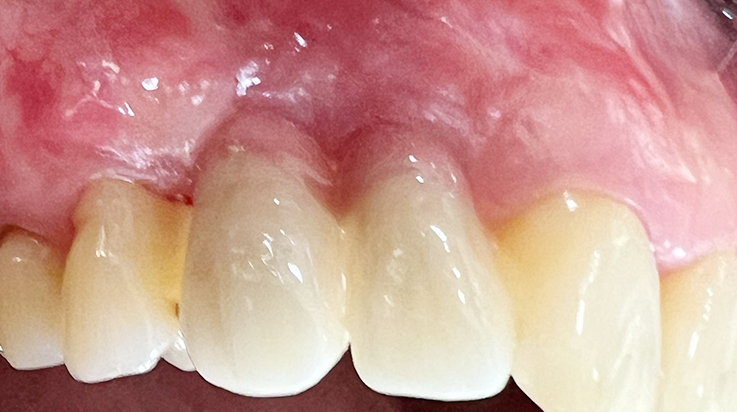

A surgical procedure using resorbable membrane

• A surgical procedure using resorbable membrane 3